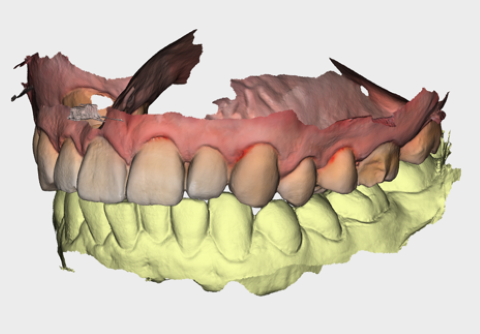

**Mesh rendering with/without texture**